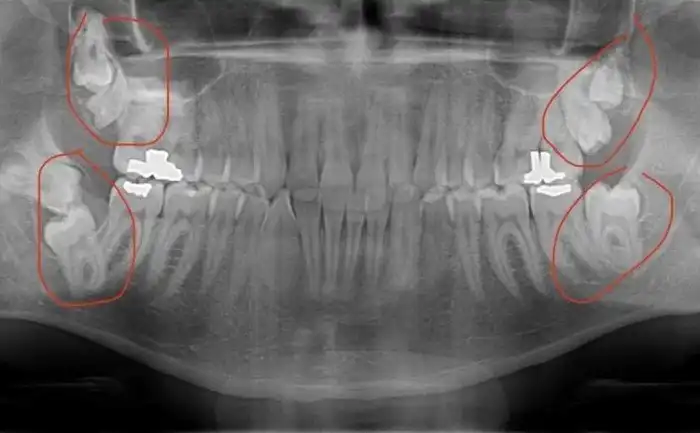

Запас мудрости

Сейчас у многих вырастает только 1-2 зуба мудрости. Или вообще ни одного. А у автора этого фото их целых 7. Великолепная семерка, которую он, впрочем, удалил. Во избежание, так сказать.